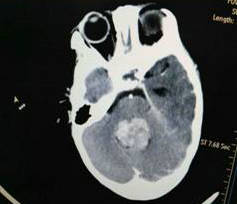

当日19时,在寄托了无限希望的手术室里,一场挽救生命的战争悄无声息地展开了。分分秒秒对患儿都至关重要,压迫脑脊液循环通路的肿瘤早一分钟被切除,脑疝的风险就会早一分钟消失,患儿就会早一分脱离生命的危险。神经外科二病区吴建珩副主任医师迅速而精准地进行着每一步手术操作,切皮、开颅、处理硬膜、显露、游离肿瘤边界,术中所见的肿瘤组织与术前所做的增强CT检查一致,位于第四脑室,严重堵塞了脑脊液的循环通路,确定是室管膜瘤,神经外科二病区主任单峤在显微镜下小心翼翼分块切除肿瘤,最后完全清理了第四脑室内的肿瘤组织,随着脑脊液从第四脑室缓缓流出,患儿的生命之门被打开了。

从开始麻醉到手术结束仅仅用了两个半小时的时间,出血仅100ml。手术结束后患儿转入ICU。“手术过程顺利,肿瘤组织被完全切除,脑脊液的循环通路打开了,应该会有一个不错的结果”,单峤主任第一时间向患儿的父母报告了这个好消息。

术后:肿瘤完全切除